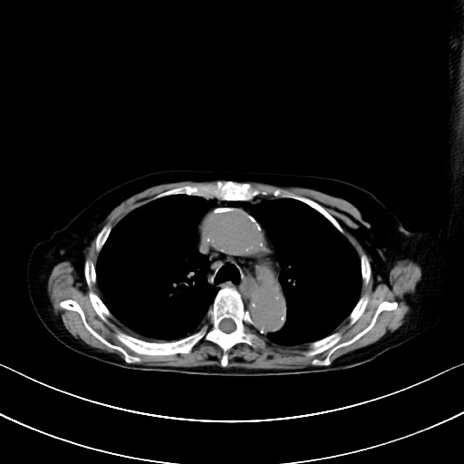

症例40(横断像)他院1日前

横断像

他院CT